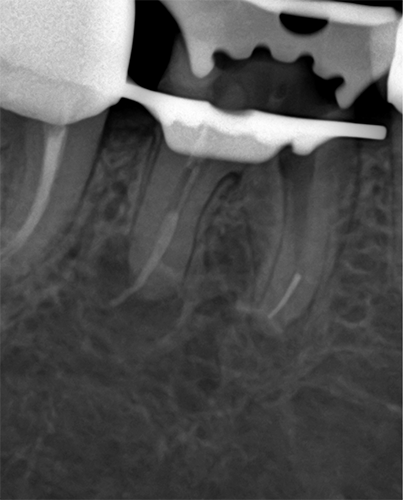

정밀진료의 시작,

미세현미경

보이지 않던 미세한 구조까지, 선명하게

Zumax OMS2050 미세현미경으로 육안으로는 확인하기 어려운

치근관(신경관)의 세부 구조까지 확대 관찰하며 정밀하게 진료합니다.

특히 (재)신경치료와 같이 세심한 접근이 필요한 경우,

기존 충전물 아래에 남아있을 수 있는 문제점이나 미세한 균열 등을

면밀히 파악하여 보다 정확한 치료 판단과 접근이 가능하도록 돕습니다.